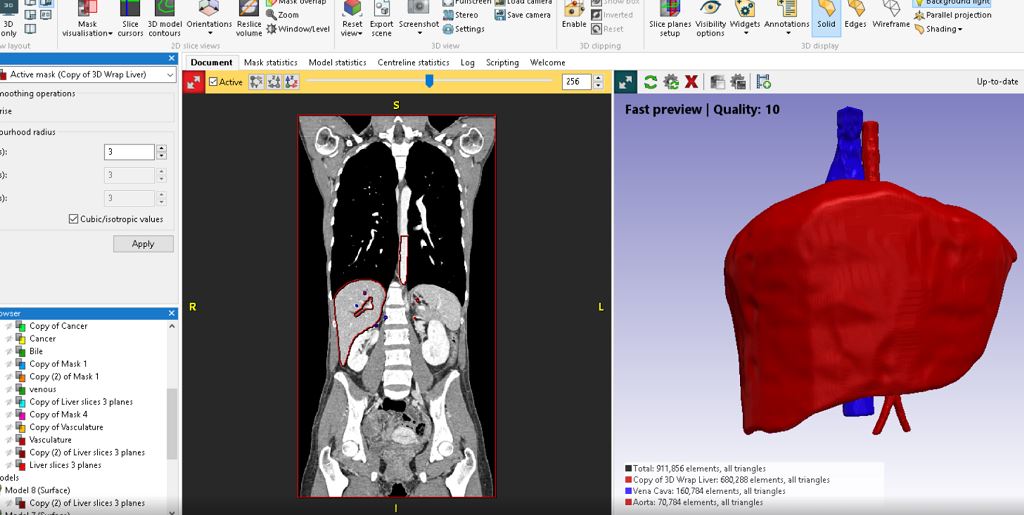

Solving Image-Based Medical 3D Printing Challenges

Medical 3D printing is becoming increasingly valuable for manufacturers and clinicians to solve patient-specific problems through tailored implants to improve diagnostic decision-making.